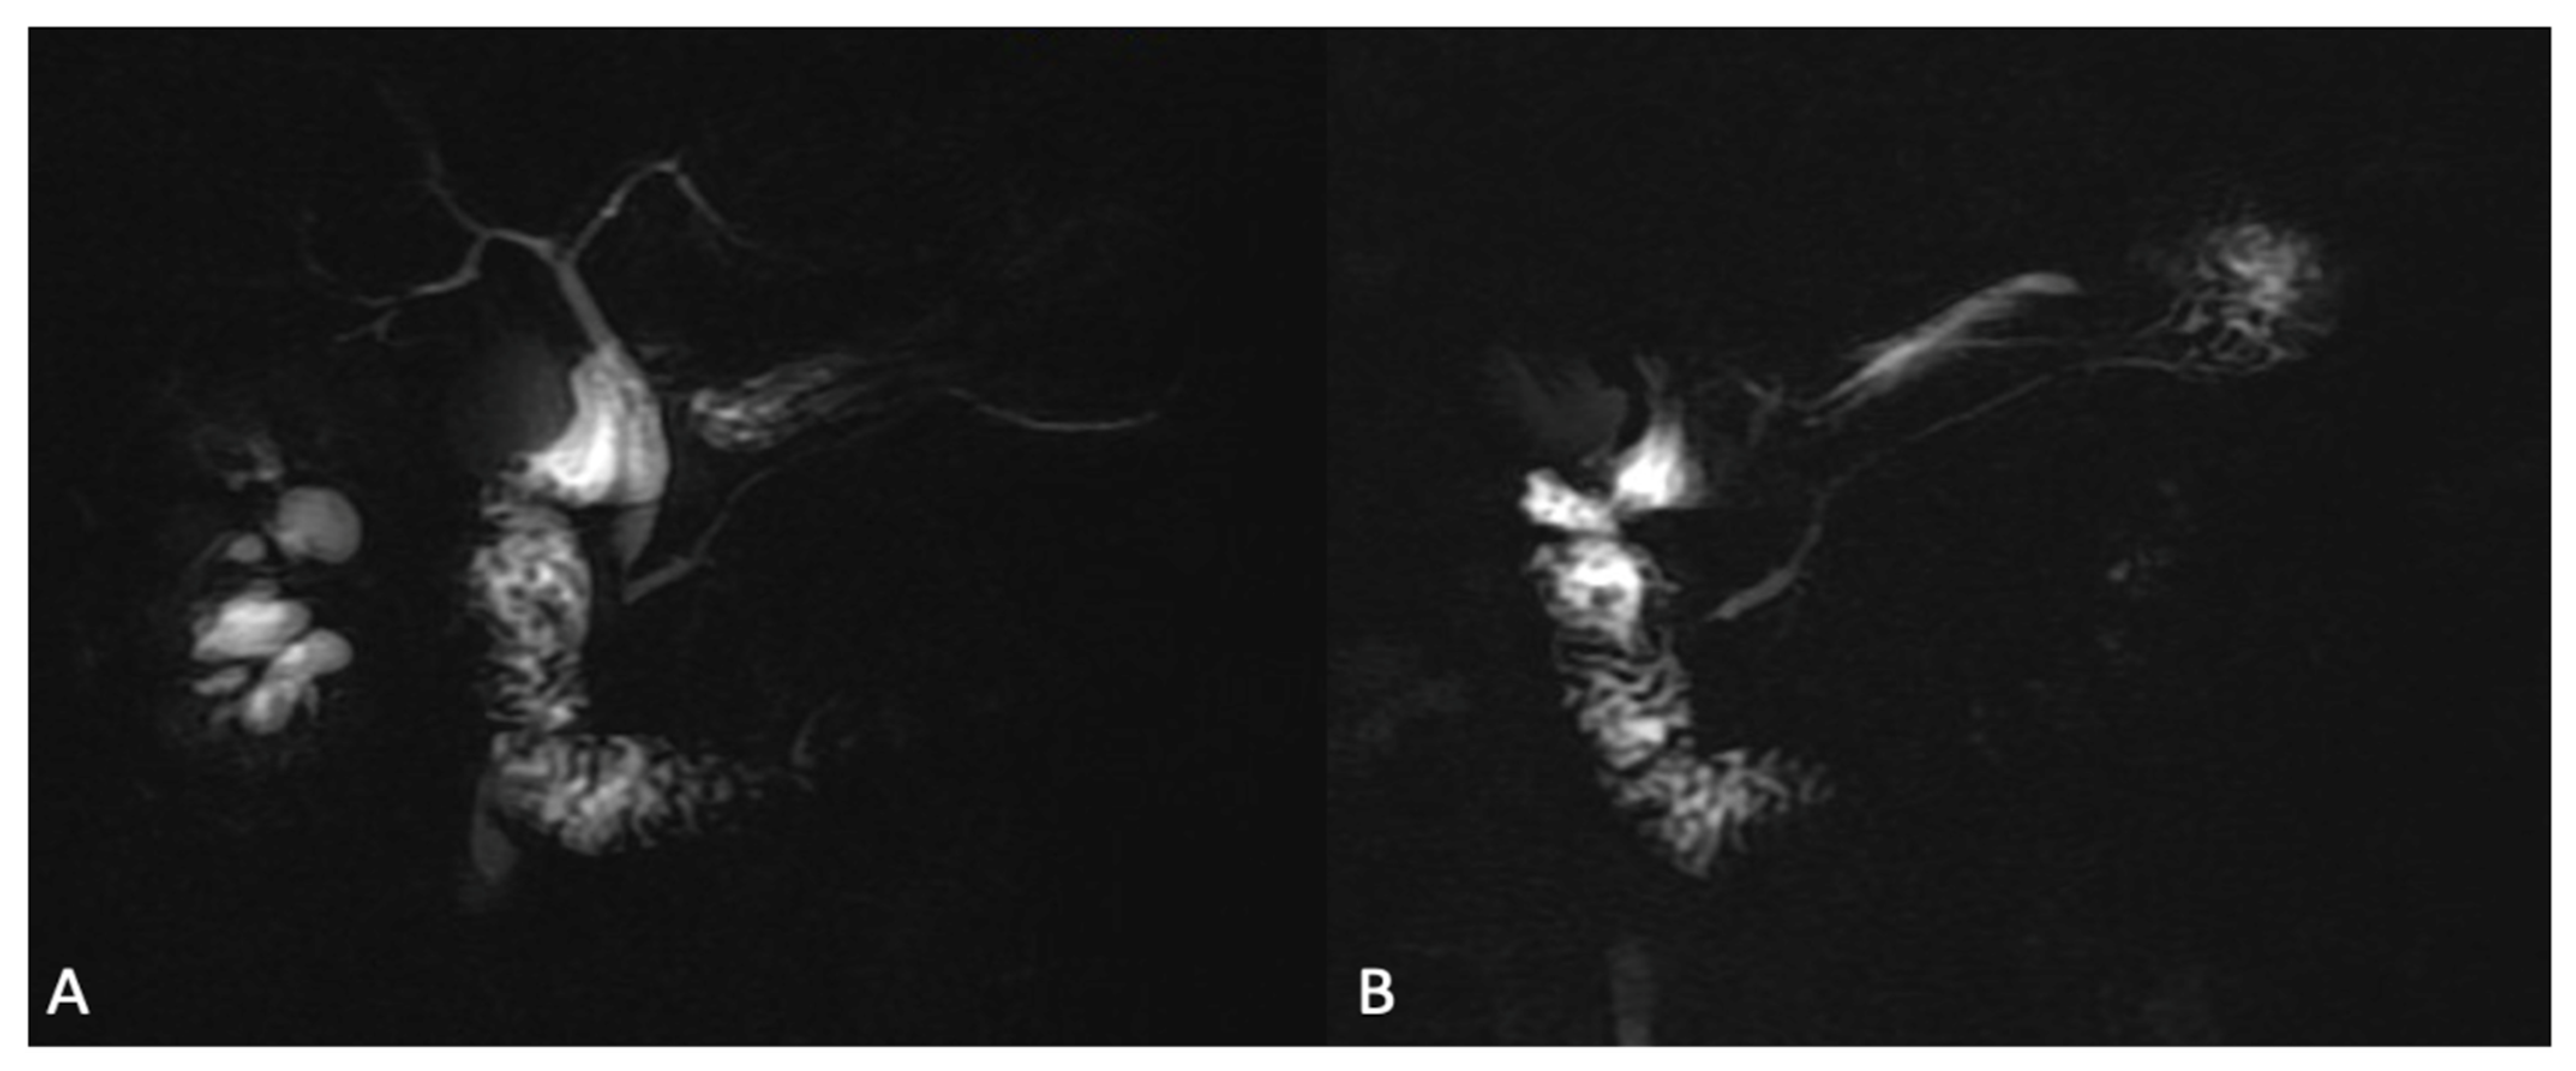

- Two-dimensional radial slab MR cholangiopancreatography after ECSA, as gadolinium reduces the signal intensity of the kidneys and renal collecting systems, which may improve the visualization of the biliary tract and pancreatic ducts (Figure 7);

- Two-dimensional radial slab MR cholangiopancreatography/high-resolution 3D MR cholangiopancreatography after HSCAs (the biliary excretion may darken the bile ducts and degrade biliary duct visualization, potentially rendering these images nondiagnostic);